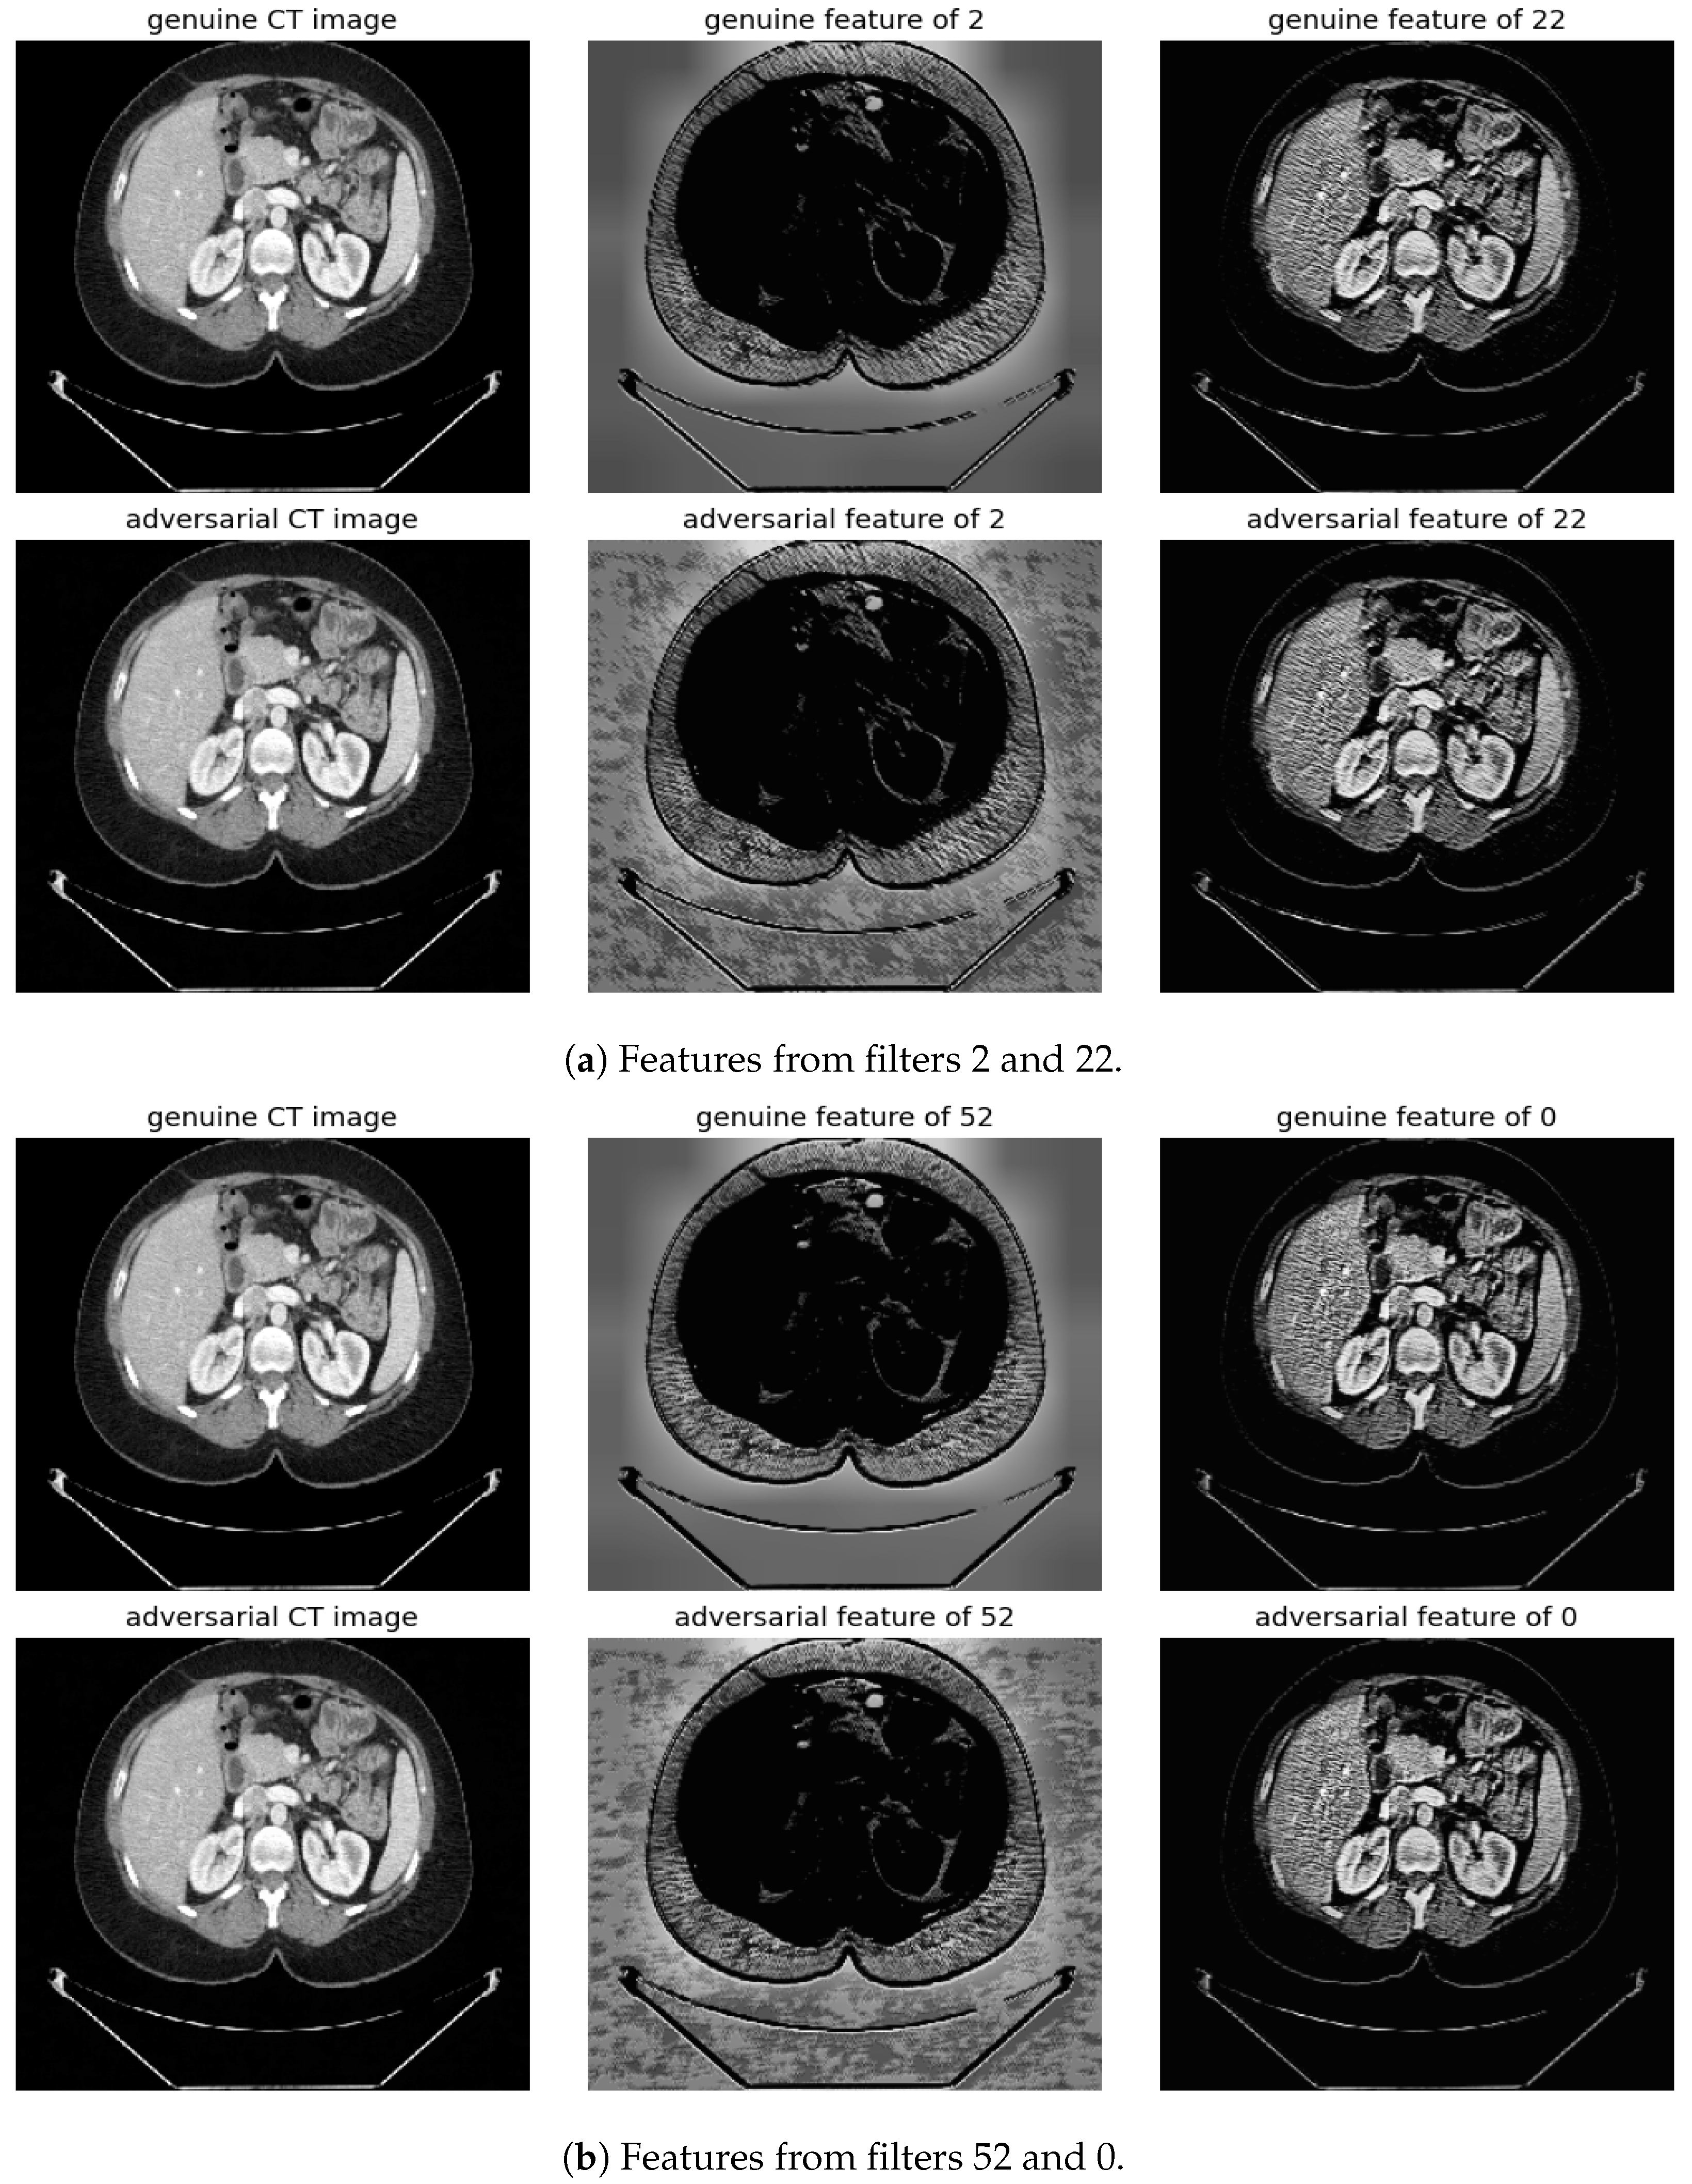

Randomly selected genuine CT samples, alongside their adversarial versions, are displayed in Figure 9, Figure 10 and Figure 11. The adversarial samples were generated using FGSM, BIM, and SMIA attack methods, each with an epsilon of 0.01. While BIM and SMIA used 5 iterations, FGSM did not. These samples represent the most challenging scenarios for human visual detection. Despite the modest epsilon value, as indicated in Table 3, the adversarial attacks have a subtle but pronounced effect. Such slight modifications can lead to major diagnostic inaccuracies potentially impacting patient care.

To address this, histogram equalization as feature post-processing is applied. The visual representations underscore that while genuine and adversarial samples might appear similar to the naked eye, post-processing brings forth distinct feature differences when employing the most sensitive filters from 2 and 52. Perturbations, especially noticeable in the background of the adversarial samples, are frequently highlighted by these filters. Conversely, features processed with filters from 22 and 0, deemed less sensitive in prior analyses, fail to offer a stark visual contrast.

Figure 11. Visualization under SMIA Attack: Comparison of features from the first layer between genuine and adversarial samples for the most sensitive (filters 2 and 52) and least sensitive (filter 22 and 0) filters.